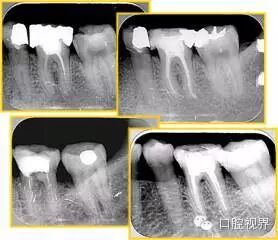

7. 器械折断

右图及下图为器械折断的 X 线片。箭头处示折断器械。

口腔H锉怎么消毒根管治疗的细节把握(细节决定成败)_https://www.jmylbn.com_新闻资讯_第27张 口腔H锉怎么消毒根管治疗的细节把握(细节决定成败)_https://www.jmylbn.com_新闻资讯_第28张

解决方法:( 1 )取出。( 2 )通过。( 3 )重新确定工作长度,充填。( 4 )根尖手术。

器械折断可以不用取出,取出的原因多是患者心理因素。留在里面的器械关键是进行消毒,预防性使用抗感染药物,预防感染。